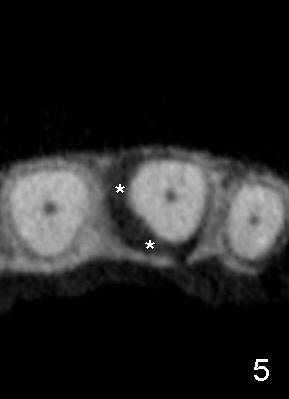

A 60-year-old lady had an abscess mesial to #9 six years ago (Fig.1,2 <), treated as a perio lesion by laser (Fig.3) and osseous surgery without bone graft (Fig.6, followed by CT exam revealing semi-circumferential bone loss (Fig.4,5). When the perio treatment failed, attention was paid to endo aspect (Fig.7-9). In fact the pulp was found to be vital when access to root canal therapy was made. As expected, the treatment failed again. The palatal fistula persisted. The infection was suspected to be a source of remote immediate implant site (#30). The tooth #9 was extracted. It appears that there is a semilunar crack line in the linguomesial root (Fig.12). When the socket healed 2 weeks post extraction (Fig.10), the #30 buccal defect was debrided with bone graft. There was no bone resorption 4 weeks post extraction (Fig.11); a 4.5x17 mm implant was placed (Fig.13-15). An immediate provisional was fabricated (Fig.16-18). Fig.19,20 were taken 3 months post implantation and 7 months post cementation, respectively. Dense bone forms around the implant coronally 4 years 5 months post cementation (Fig.21), while the gingiva is healthy palatally (Fig.22) and buccally (Fig.23).